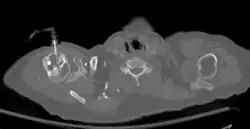

The needle is inserted through the bone's hard cortex and into the soft marrow interior, which allows immediate access to the vascular system. The IO needle is positioned at a 90-degree angle to the injection site, and is advanced through manual traction, impact driven force, or power driven. Each IO device has different designated insertion locations. The most common site of insertion is the antero-medial aspect of the upper, proximal tibia as this site lies just under the skin and is easily located. Other insertion sites include the anterior aspect of the femur, the superior iliac crest, proximal humerus, proximal tibia, distal tibia and the sternum (manubrium).[1] Although intravascular access is still the preferred method for medication delivery in the prehospital area, IO access for adults has become more common. As of 2010, the American Heart Association no longer recommends using the endotracheal tube (ET) for resuscitation drugs, except as a last resort when IV or IO access cannot be gained.[1] ET absorption of medications is poor, and optimal ET drug dosings are unknown. IO administration is becoming more common in civilian and military pre-hospital emergency medical services (EMS) systems globally.[11]